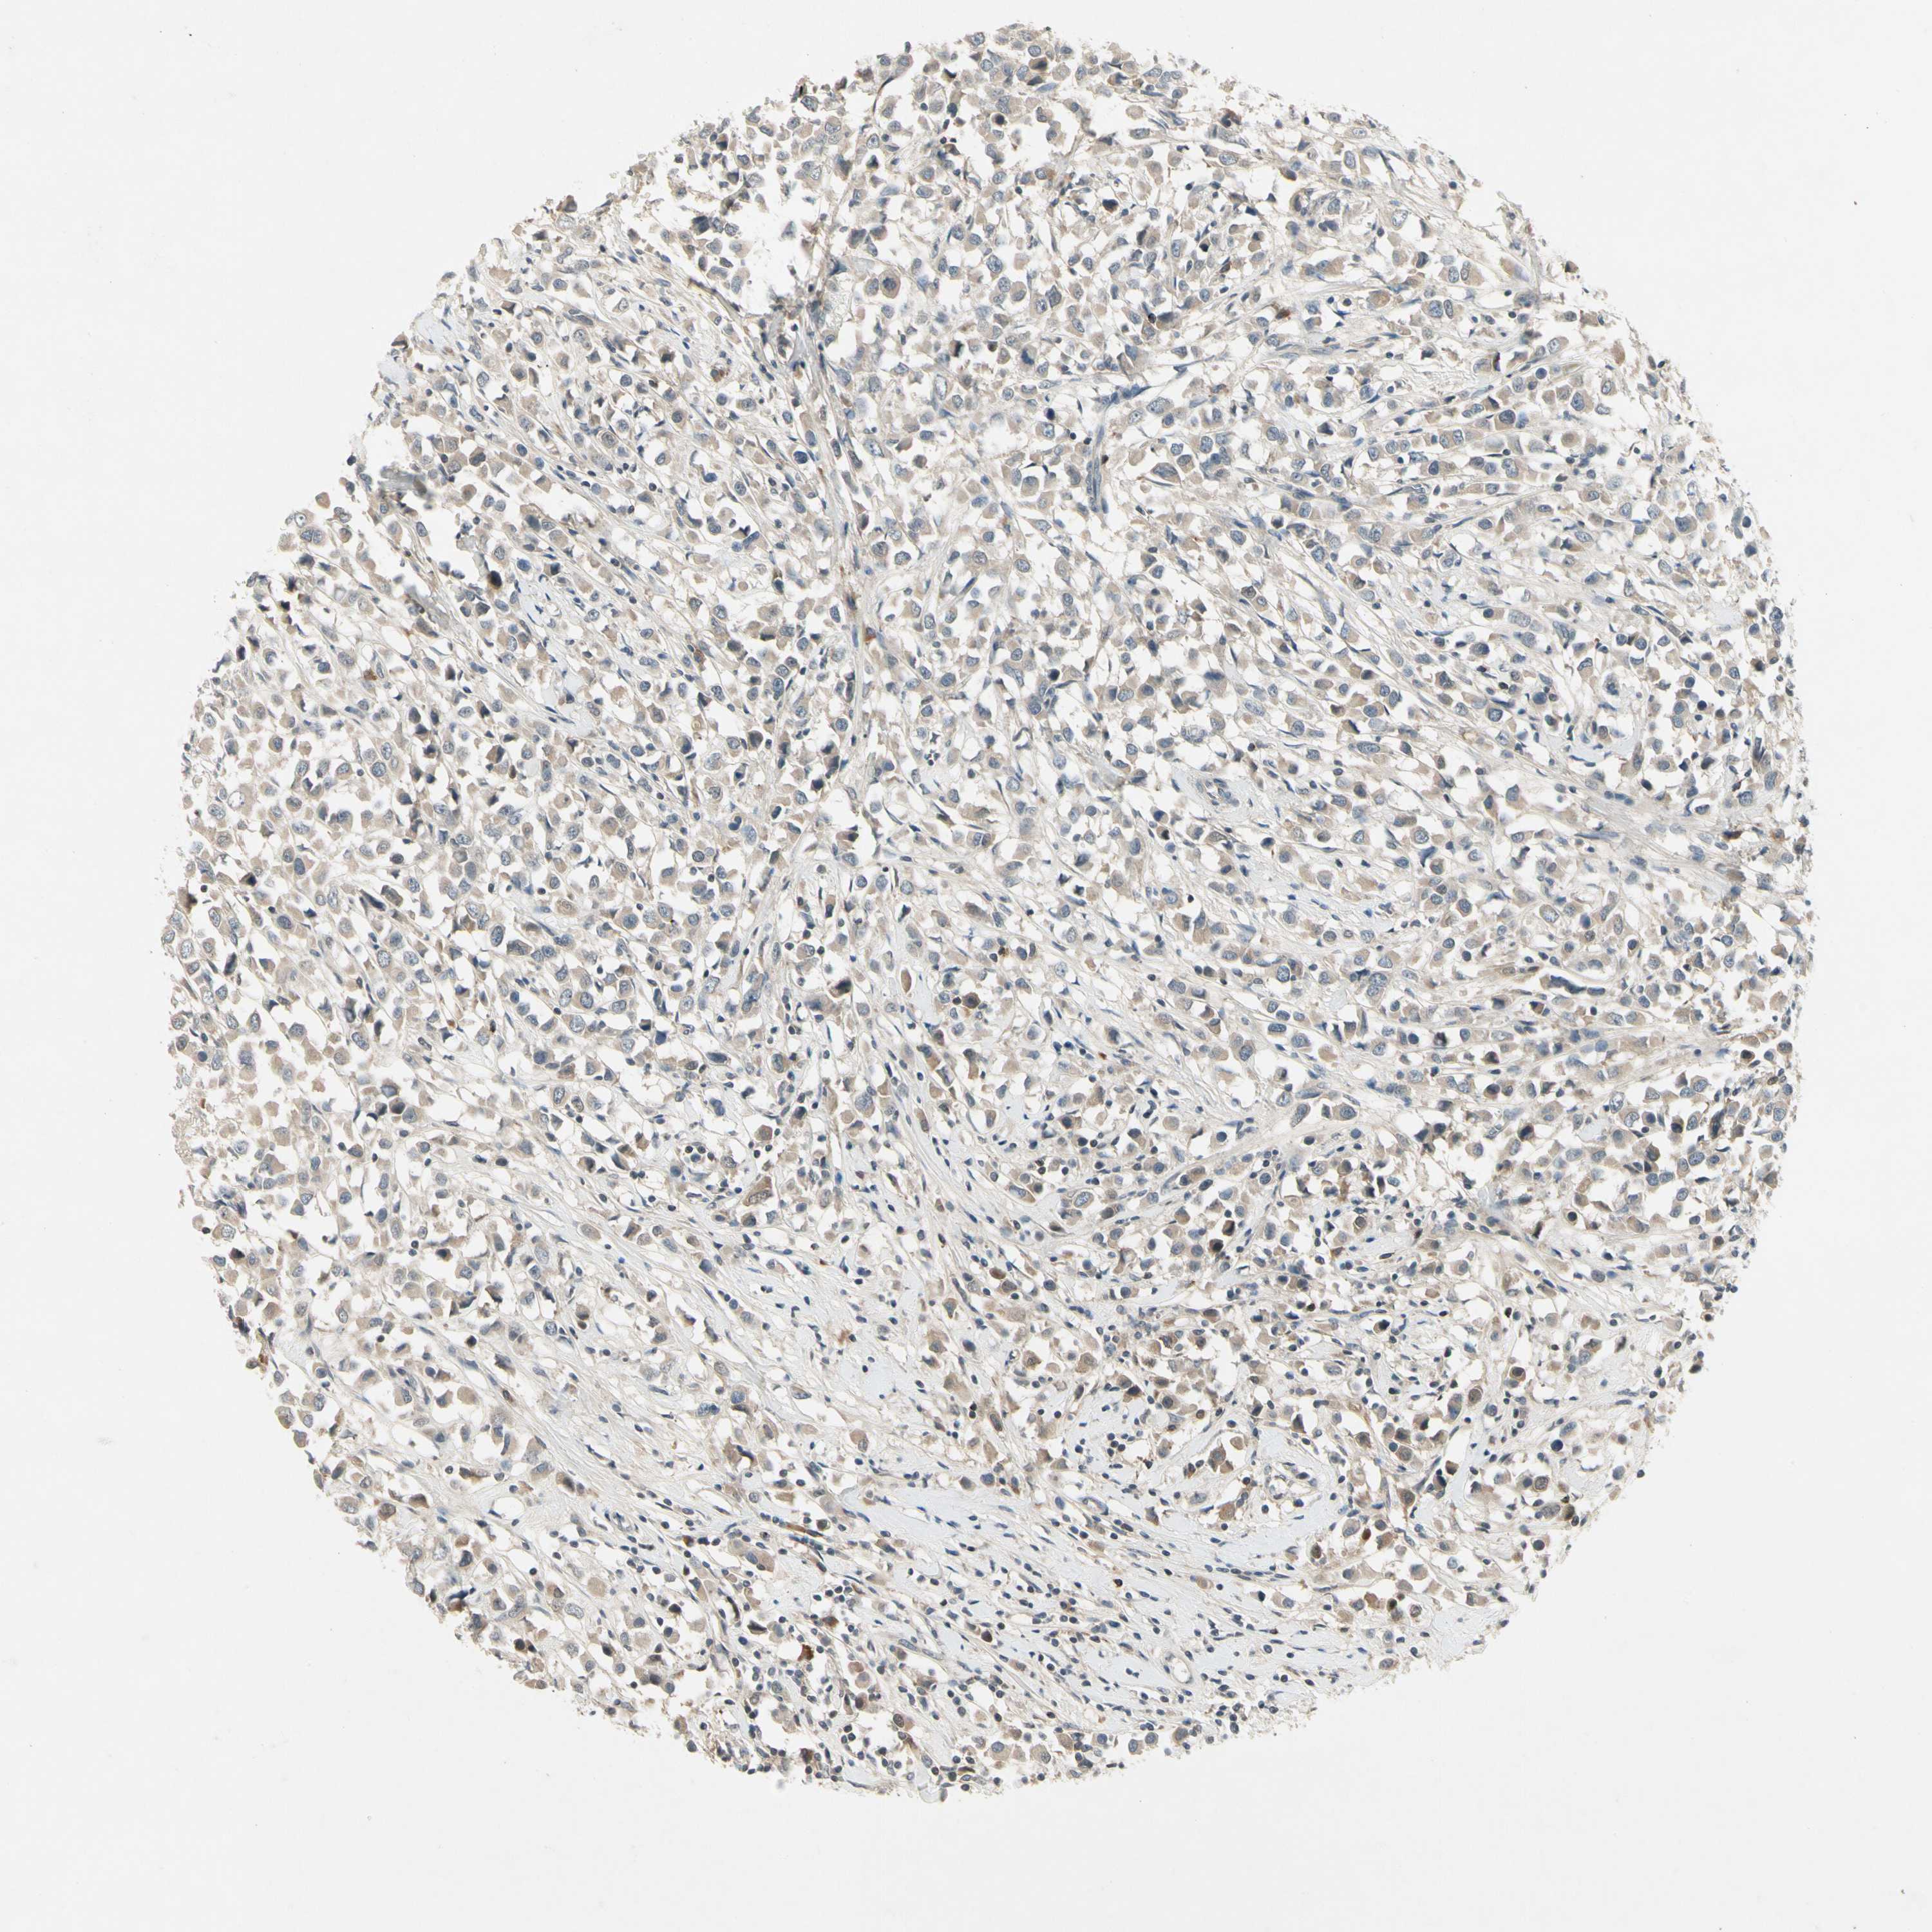

CANCER BREAST CANCER Show tissue menu

BRCA TCGA BRCA VALIDATION PROTEIN EXPRESSION

Breast cancer

Human cancer